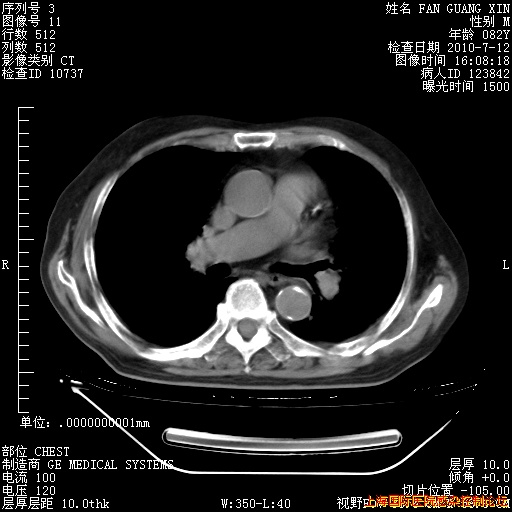

今天CT

整整相隔30天的肺部CT好像有所好转啊。甲强龙减量第3天,需要观察体温。

海管,自昨日你和我通完话后,不知您岳父消化道症状有无缓解?体温怎样?阅读7.12日胸部ct,个人认为目前激素治疗是有效的,甲强龙减量是适宜的。因在抗痨治疗,需密切观察肝功、肾功能和血常规。不过,老年、长期住院和大量使用激素,很担心菌群失调发生